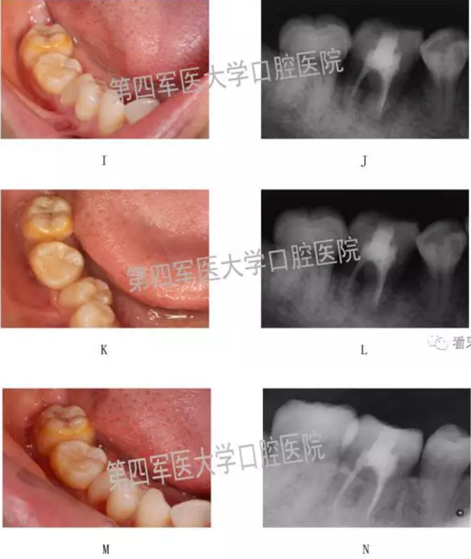

四、典型病例: